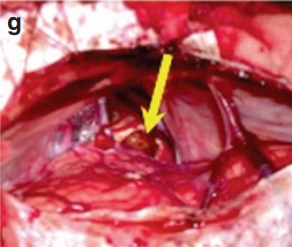

这个14岁的女孩从3岁开始就经常出现不明原因的失神发作。手术前两个月,患者突然出现持续癫痫状态,需要紧急治疗,并开始进一步诊断。磁共振成像(MRI)显示出出血性顶盖病变梗塞性脑积水。立即进行内镜下三脑室造瘘术后,患者未出现其他并发症,也没有额外的癫痫发作发生。术前T2w轴位(a)和矢状位(b)MRI显示出出血性占位性顶盖病变。

经幕下小脑上入路入路手术暴露,发现病变为典型的海绵状血管瘤,且伴有新鲜的病灶内出血(c)。

术后MRI显示该血管畸形被完全切除(d和e)。

术后,患者术后神经系统完好,微笑如初,回归学业。